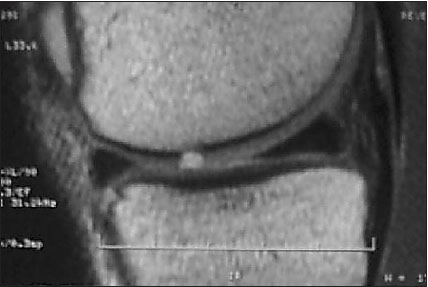

Todos los pacientes que realizaron su RM de rodilla en el Servicio de Diagnóstico por Imágenes del Hospital Británico, y luego fueron operados de su rodilla en el mismo Centro durante el mes de Abril de 2009, fueron incluidos en el presente trabajo. Es un estudio con un diseño transversal, con recolección de datos retrospectiva, nivel de evidencia III. Un total de 43 pacientes fueron incluidos. Dos pacientes fueron excluidos del análisis por alteración de la imagen de resonancia, uno por artefacto del movimiento durante el estudio y el otro por artefacto producido por material de osteosíntesis colocado en la rodilla en una intervención previa. De los 41 pacientes evaluados en el estudio, el promedio de edad fue de 50 años (21-71). Fueron 27 hombres y 14 mujeres evaluados. El intervalo de tiempo promedio entre la realización de la RM y la cirugía fue de 63 días (6-275 d). Veintinueve pacientes (70,73 %) fueron intervenidos dentro de los 2 meses de realizada la RM. Se realizó una revisión de las historias clínicas para corroborar que ningún paciente refirió alguna lesión durante ese intervalo de tiempo. En todos los casos se realizó una RM con un equipo Philips de 1,5 Tesla, realizando en todas ellas cortes de reconstrucción axial, coronal y sagital, para evaluar adecuadamente la articulación en toda su extensión. Cada estudio de RM fue analizado en forma retrospectiva por dos observadores ciegos de los resultados obtenidos luego en la cirugía, ambos trabajaron en forma conjunta. Uno de los evaluadores (M.C) es médico de planta del Servicio de Diagnóstico por Imágenes del Hospital (especialista en RM músculo esquelética); el otro evaluador (L.C) es Jefe de Residentes de Diagnóstico por Imágenes del Hospital. Ambos estudiaron cada caso en particular, y debían valorar el cartílago en cada zona articular y establecer un único resultado. Seis superficies articulares fueron evaluadas: rótula, tróclea, cóndilo femoral medial y lateral, platillo tibial medial y lateral. El cartílago articular fue clasificado en la RM y en la artroscopia de acuerdo a la clasificación de Johansson. (7) El Grado 0 indica cartílago intacto; grado 1 ablandamiento o edema de cartílago; grado 2 fibrilación de cartílago; grado 3 ulceración superficial o fisura que comprometen menos del 50% del espesor del cartílago; grado 4 ulceración profunda o fisuras que comprometen ás del 50% del espesor de cartílago; grado 5 lesión de espesor completo con hueso expuesto; grado 6 lesión en espejo, con hueso expuesto en ambas superficie enfrentadas. Todas las lesiones condrales debieron ser confirmadas en al menos 2 cortes de RM. Se confeccionó en cada caso un registro escrito de cada paciente con los grados de lesión condral en cada superficie. (Ver Figs. 1 a 4)

Figura 1: Lesión condral de espesor completo en RMN. Corresponde a un grado 5.